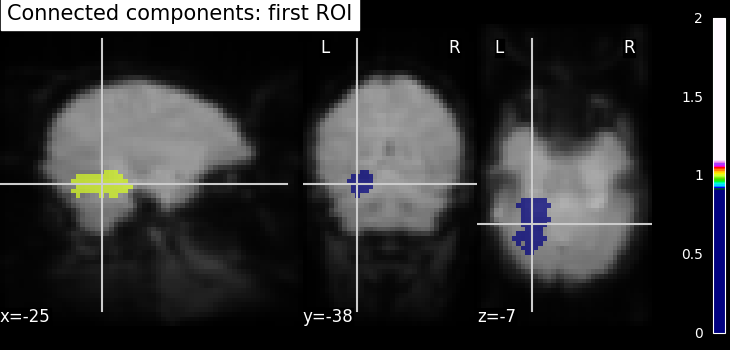

Finally, we end with splitting the connected ROIs to two hemispheres into two separate regions (ROIs). The function scipy.ndimage.label from the scipy Python library.

Identification of connected components - The function

scipy.ndimage.label from the scipy Python library identifies

immediately neighboring voxels in our voxels mask. It assigns a separate

integer label to each one of them.

from scipy.ndimage import label

labels, _ = label(dil_bin_p_values_and_vt)

# we take first roi data with labels assigned as integer 1

first_roi_data = (labels == 5).astype(np.int32)

# Similarly, second roi data is assigned as integer 2

second_roi_data = (labels == 3).astype(np.int32)

# Visualizing the connected components

# First, we create a Nifti image type from first roi data in a array

first_roi_img = new_img_like(fmri_img, first_roi_data)

# Then, visualize the same created Nifti image in first argument and mean of

# functional images as background (second argument), cut_coords is default now

# and coordinates are selected automatically pointed exactly on the roi data

plot_roi(first_roi_img, mean_img, title="Connected components: first ROI")